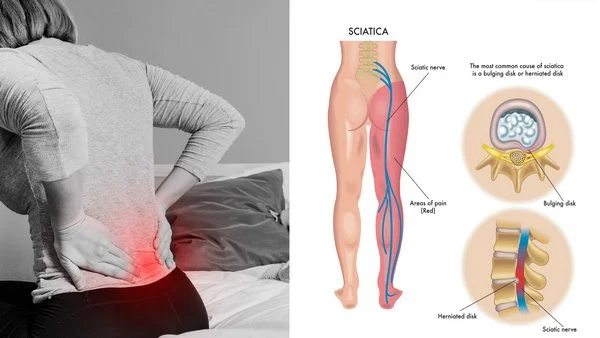

He is dedicated to providing personalized treatment plans for conditions such as back pain, slipped disc, sciatica, spinal stenosis, cervical and lumbar spine disorders, and degenerative spine diseases. Dr. Agrawal combines modern medical technology with a compassionate approach, focusing on accurate diagnosis and patient education at every step.

Sciatica / Lumbar Disc Prolapse Treatment